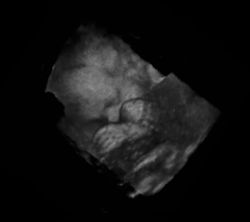

Mehrdimensionale Anwendung

Als weitere Applikation wurde in den letzten Jahren (Anfang des 21. Jahrhunderts) die dreidimensionale Echografie entwickelt. Der 3D-Ultraschall produziert räumliche Standbilder, und der 4D-Ultraschall (auch genannt Live-3D: 3D plus zeitliche Dimension) lässt dreidimensionale Darstellung in Echtzeit zu. Für ein dreidimensionales Bild wird zusätzlich zum Scan in einer Ebene ein Schwenk der Ebene vollzogen. Der Flächenscanwinkel wird gleichzeitig mit dem zweidimensionalen Bild abgespeichert. Eine weitere Möglichkeit besteht in der Verwendung einer zweidimensionalen Anordnung von Ultraschallwandlern in einem sogenannten Phased Array, bei der nicht mechanisch, sondern elektronisch ein Schwenk des Strahles durchgeführt wird.

Die Daten werden für die Bildverarbeitung und Visualisierung von einem Rechner in eine 3D-Matrix eingetragen. So können dann Darstellungen von Schnittebenen aus beliebigen Blickwinkeln auf das Objekt erzeugt oder virtuelle Reisen durch den Körper gestaltet werden. Um Bewegungsartefakte durch die Herztätigkeit zu vermeiden, wird die Aufnahme mittels EKG gesteuert.